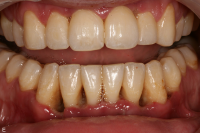

Gingivit är tandköttsinflammation som visar sig genom marginal blödning vid sondering, men där tanden ej har någon förlust av käkbensfäste.

Diagnosen gingivit används vid tänder med marginal inflammation och blödande tandkött, men ingen förekomst av marginal benförlust. Fickdjup 1–3 mm, pseudofickor kan förekomma upp till 5 mm.

Ödematös, rodnad och blödande gingiva.

Gingival hälsa på intakt och reducerat parodontium.

Parodontal stabilitet karakteriseras av framgångsrik behandling genom kontroll av lokala och systemiska riskfaktorer, vilket resulterat i

• minimal blödning vid sondering (BVS < 10 % av tandytorna)

• fickdjup < 3 mm

• ingen progressiv parodontal nedbrytning/vävnadsförlust

• optimal förbättring i övriga kliniska parametrar hos behandlad parodontitpatient.